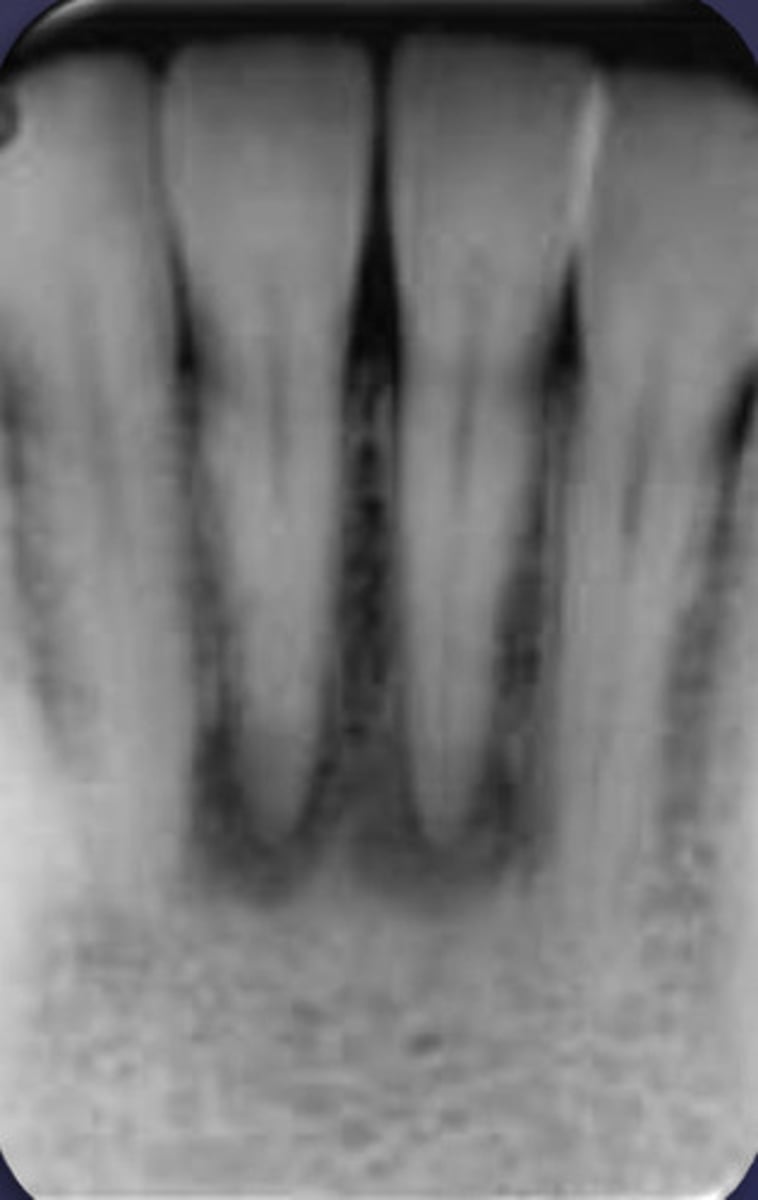

ID the cyst:

- Lesion is superimposed over the apices of maxillary central incisors

- No changes in apical structures of these teeth (lamina dura, PDL)

- Vital teeth

- May displace these teeth

nasopalatine duct cyst